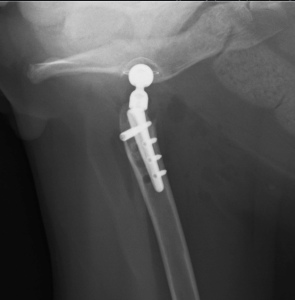

2022年3月11日 再び跛行し始めたとのことで、mini THR Cementless法 実施

症状に合わせて今後の治療を検討しておりましたが、2週間ほどしてから左後肢の跛行が見られるようになったため、外科手術を行いました。不正癒合していた骨頭部を整復することが困難と思われ、” 股関節人工関節全置換術 “を実施しました。

骨頭骨折や股関節脱臼などで整復が困難な場合、”骨頭切除手術”が選択されることがあります。しかし今回は、数年前からトイ犬種用の THR Cementless インプラントが発売されたこともあり、当院で初めて「猫に対してのTHR Cementless法」を行うこととなりました。